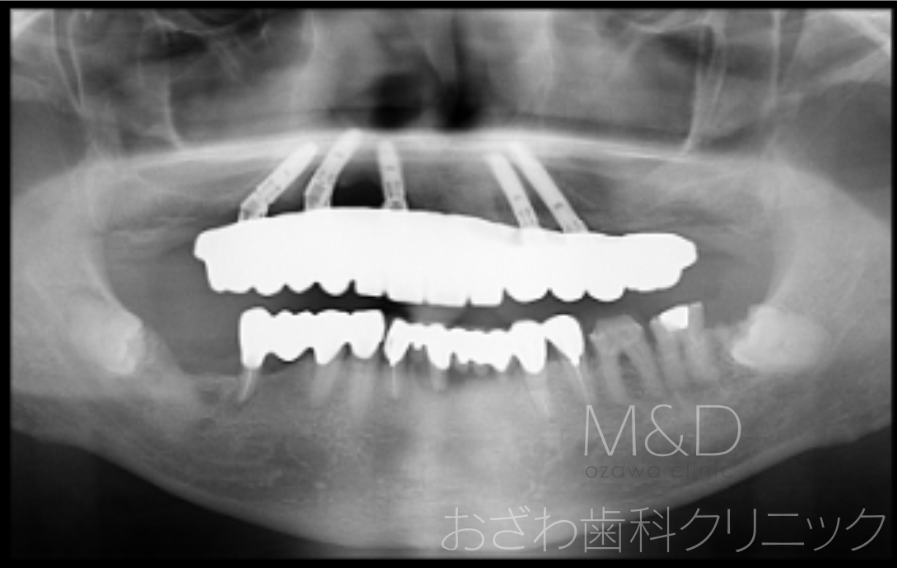

術後

上顎残存歯の抜歯、上顎5本(オールオン5)インプラント

(上顎即時負荷:オペの日に仮歯が入ります)